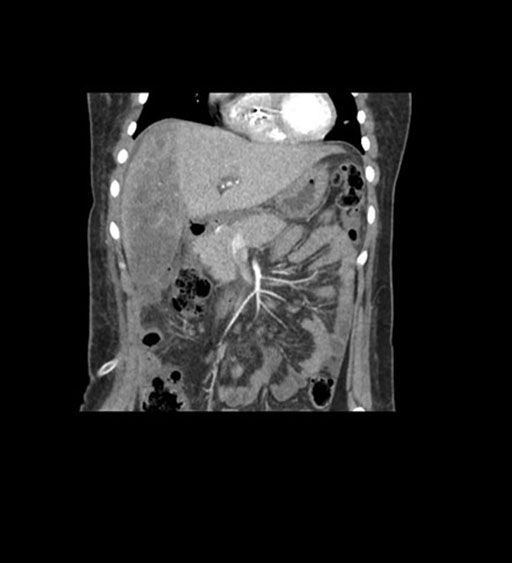

Coronal Arterial